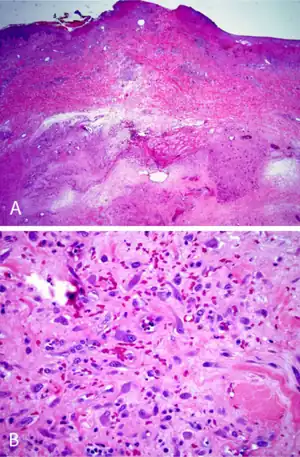

On gross examination, IF tumors are typically white-yellow masses with central necrosis (i.e. areas of dead or dying cells), and areas containing cysts and/or old, dried hemorrhages.[6] The tumors are often poorly circumscribed, have an infiltrative appearance, may be multinodular, and lie in subcutaneous tissue but may also involve the dermal layer of the skin[8] and/or the reticular dermis.[6] Microscopic histopathological studies of IF tissues report the characteristic presence of a distinct zonal appearance, i.e. the presence of central zones of fibrinoid necrosis and areas of cyst-laden necrosis in a hypocellular background surrounding by a zone of granulation tissue (i.e. connective tissue containing microscopic blood vessels) populated by atypical, swollen fibroblasts, myofibroblasts, and/or macrophages.[4]

Immunohistochemistry analyses of IF tumors often show the presence of fibroblasts, fibroblast-like cells, and or other types of cells that in a percentage of cases express smooth muscle actin proteins, CD68 protein,.[6] desmin protein,[4] vimentin protein, and collagen type IV protein, but not keratin, S100,[6] calponin, or CD34 proteins.[1] The finding that a tumor's cells have some of these patterns of protein expression can help support the diagnosis of IF.[6]